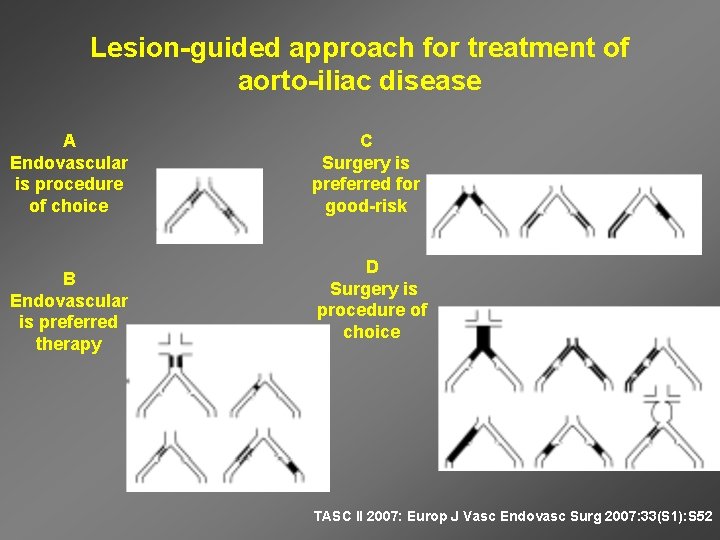

Lesion-guided approach for treatment of aorto-iliac disease A Endovascular is procedure of choice B Endovascular is preferred therapy C Surgery is preferred for good-risk D Surgery is procedure of choice TASC II 2007: Europ J Vasc Endovasc Surg 2007: 33(S 1): S 52